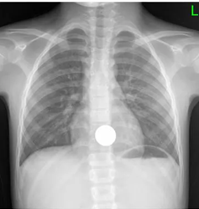

适用于金属或高密度异物,胸、腹部正侧位X线片可了解异物数量、大小、形态及位置,硬币类圆钝消化道异物需随访X线,以观察异物的位置,是否存在嵌顿的情况。

正侧位显示硬币的位置位于上消化道